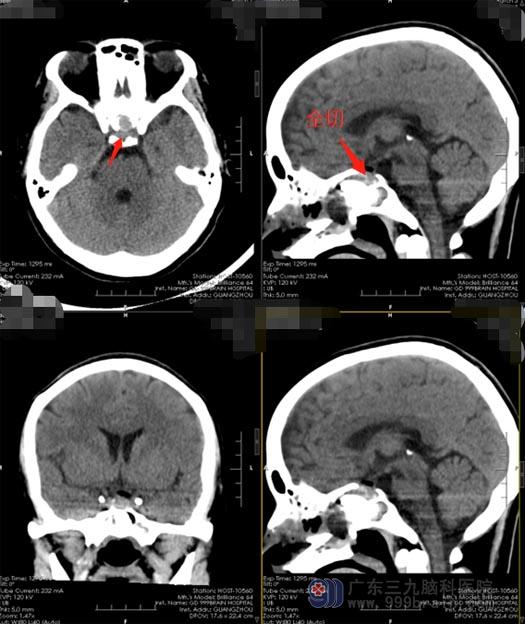

知道了原因,小刘非常紧张,“喝水多居然是脑子里出现了问题”,她忐忑不安地在网上搜集相关的疾病知识,越看越害怕。在朋友的安慰和介绍下,小刘来到了广东三九脑科医院神经外五科,进一步垂体影像检查发现:垂体前叶上缘占位性病变,考虑 Rathke’s囊肿可能性大,待排微腺瘤囊变;CT血管成像检查意见:鞍区结节状占位性病变。